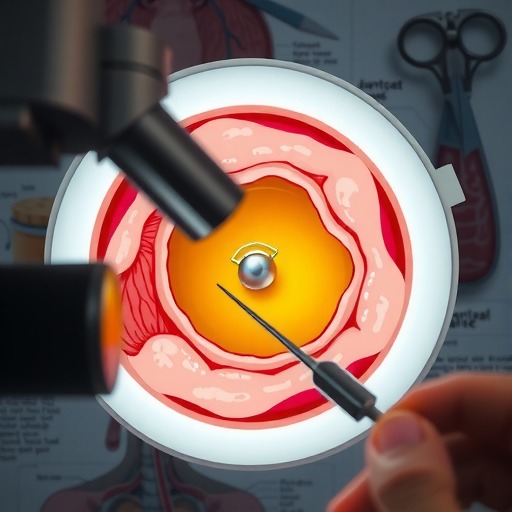

今晚19:00《CAUVTH2025临床能力提升系列线上公益课程 | 如何找到脓包里“飞来”的异物 》 将由中国农业大学动物医院影像专科吴璇医生与大家分享!

1.经典病例引入;

2.常见异物的种类;

3.超声扫查推荐流程;

4.脓肿及异物超声征象;

5.如何超声引导取出异物。

通过本次课程,参与者将能够:掌握脓包里异物的超声定位、实操技巧及鉴别要点,提升临床检出率。